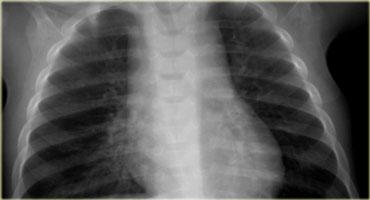

On the left a chest film of a 6-month old boy with stridor and cough.

The trachea is deviated to the left, otherwise the chest film is normal.

So there is some mass effect on the right side.